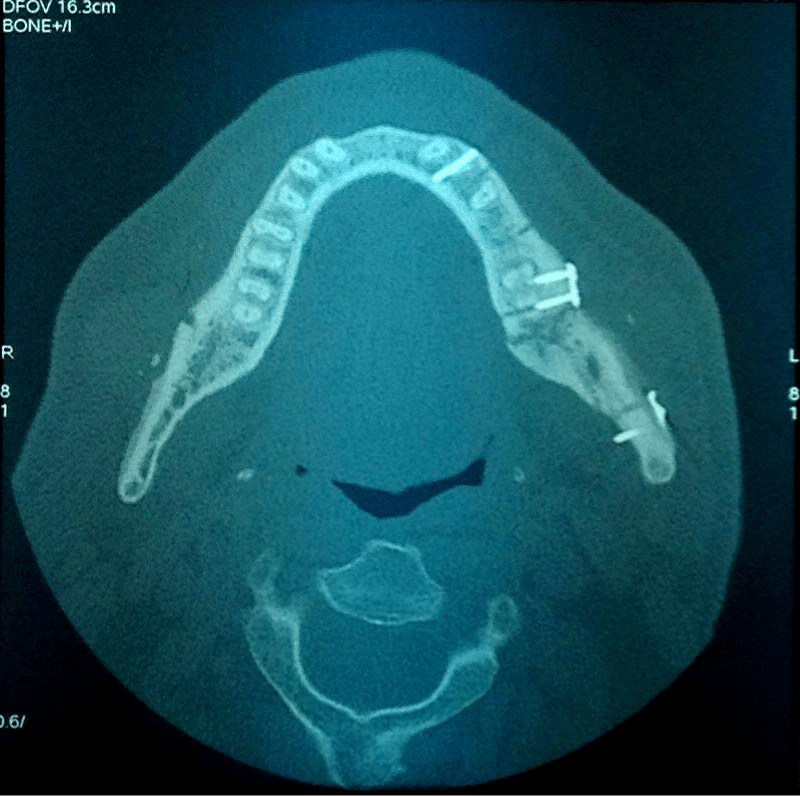

Figure 6:

3D reconstruction after the second fixation showing advanced healing.